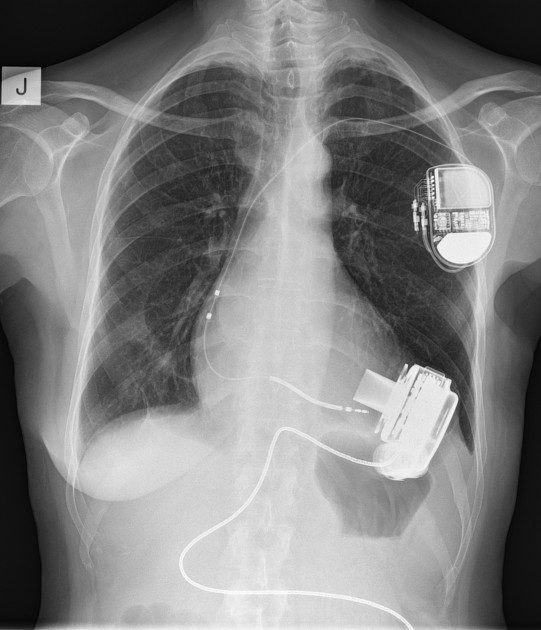

LVADStrong empowers patients and caregivers through support, education, and connection. We believe that no one should face this journey alone — and that with the right care, understanding, and community, LVAD patients can live stronger, fuller lives.